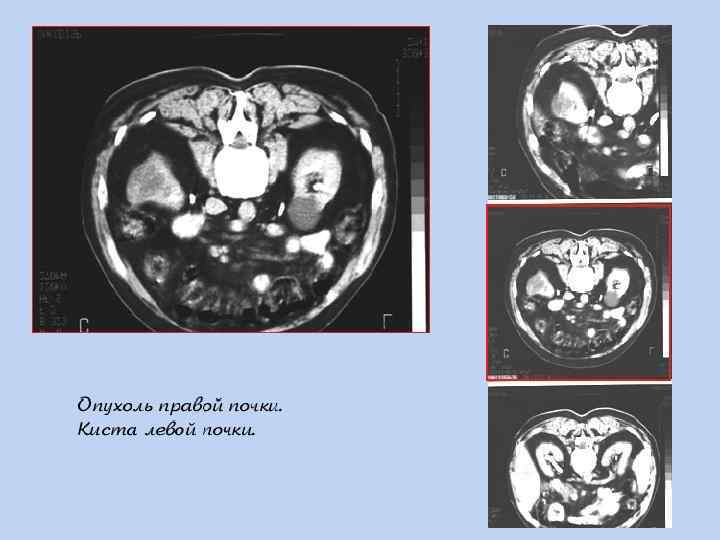

ДИАГНОСТИКА § Лабораторная диагностика «паранеопластического» синдрома (ОАК, СОЭ) и ОАМ (60 -75% гематурия); § КТ высокого разрешения с контрастом → определении стадии TNM; § в/венная урография – для определения анатомии и функции контрлатеральной почки; § УЗИ брюшной полости; § МРТ при подозрении на опухолевый тромбоз НПВ, ХПН или аллергии на в/венный контраст; § Рентгенография грудной клетки → MTS? .

КТ – опухоль левой почки с массивным распространением.

КТ – опухолевый тромбоз нижней полой вены.